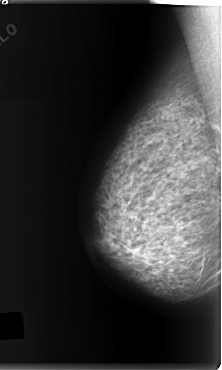

C_0148_1.RIGHT_MLO

RIGHT_CC LINES 5968 PIXELS_PER_LINE 3592 BITS_PER_PIXEL 12 RESOLUTION 50 NON_OVERLAY

RIGHT_MLO LINES 5920 PIXELS_PER_LINE 3544 BITS_PER_PIXEL 12 RESOLUTION 50 NON_OVERLAY